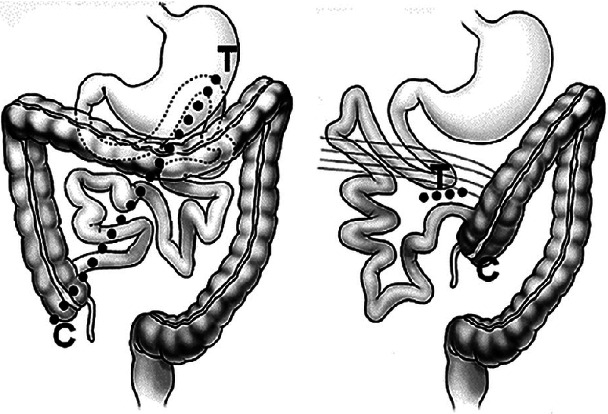

Abstract Image